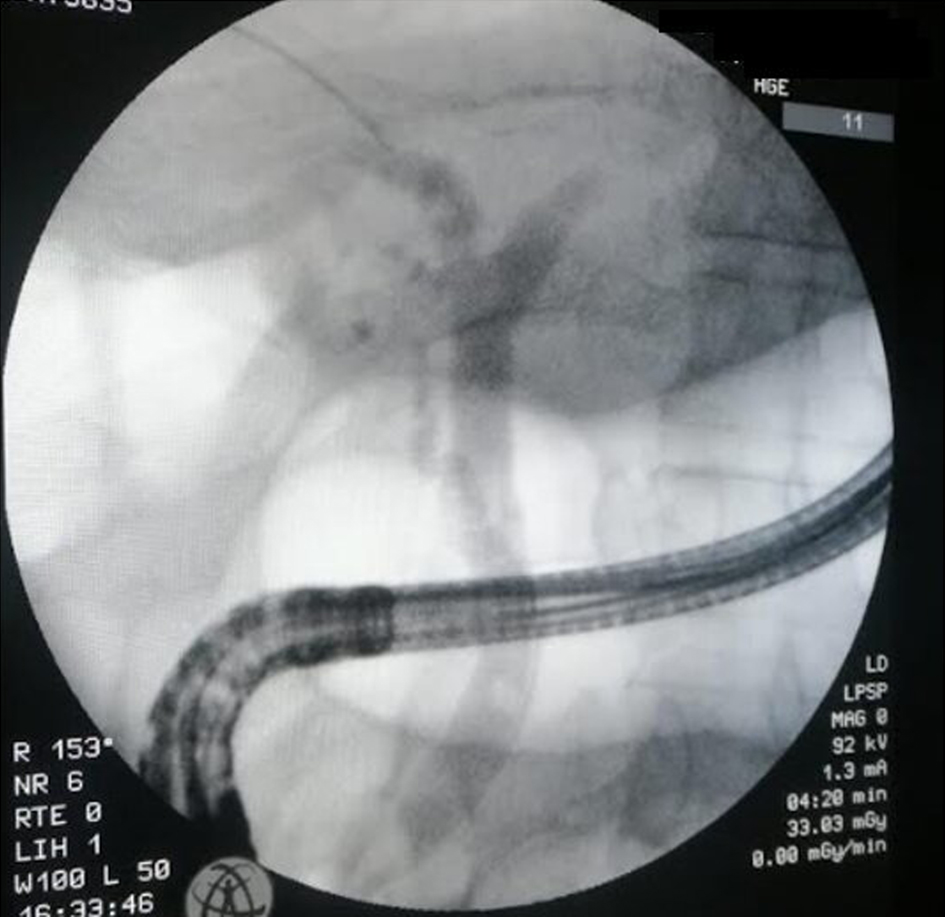

During the follow-up of the cases presenting cholelithiasis, four patients (57%) developed ABCs. One patient presented with recurrent atypical epigastralgia related to sludge and microlithiasis of the CBD and microlithiasis of the gallbladder. Two cases were complicated with biliary colic, jaundice, and biological cholestasis. Both patients had microlithiasis of the gallbladder, with associated choledochal lithiasis in one patient (Fig. 4). The other case presented biliary peritonitis with acute cholecystitis during SA treatment. The cholelithiasis in the present four cases occurred after medical treatment in three cases and before starting SA in one case (Table 2).

![]() Click for large image | Figure 4. ERCP showing choledochal lithiasis with dilation of common bile duct. ERCP: endoscopic retrograde cholangiopancreatography. |

These acute complications occurred after lanreotide treatment discontinuation in three patients (Table 2). The treatment consisted of emergency ERCP with endoscopic sphincterotomy, stone extraction (Fig. 5), and vacuity of the CBD with good clinical and biological evolution. Emergency cholecystectomy with peritoneal lavage was performed in the case of biliary peritonitis. The cholecystectomy was indicated secondarily in the other three patients. However, no cases of pancreatitis occurred in these patients with biliary disorders. The therapeutic management of these associated complications of acromegaly was decided upon by multidisciplinary meetings except for the emergency cases. In addition, the management of associated metabolic disorders, in particular obesity and dyslipidemia, was considered in all patients. Data of these cases are presented in Table 3.

According to EASL data, ABCs under treatment with SA are higher than in the general population because GS complications occur in 0.1-0.3% of asymptomatic patients [21]. In our series, acute biliary adverse effects occurred in 57% of cases with biliary lithiasis (4/7). As shown in a recent controlled randomized study, lanreotide treatment was associated with serious ABC [11]. This study reported one case of acute pancreatitis that occurred during lanreotide treatment complicated by gastro pancreatic fistula. The other cases of ABC occurred after treatment discontinuation. They included three cases of acute pancreatitis with necrotizing pancreatitis in one case, two cases of cholecystitis, one case of porcelain gallbladder, and two cases of biliary colic [11]. In our series, no case of pancreatitis was reported. However, we reported one case with biliary peritonitis, a recurrent atypical epigastralgia related to sludge, and microlithiasis of the CBD associated with a GS in one patient. The two other cases were complicated with biliary colic, jaundice, and biological cholestasis. Both patients had microlithiasis of the gallbladder, with associated choledochal lithiasis in one patient. This can explain not only the high prevalence of ABC during SA treatment but also the serious associated disorders. In our series, SA discontinuation was decided in three cases presenting ABC with an estimated median time of 11 months between the lanreotide discontinuation and the development of these complications. It has been shown that withdrawal of SA treatment can increase the risk of occurrence of ABC [23]. This can be explained by the resumption of gallbladder contractility inducing the migration of microcalculus at the origin of these complications [24].